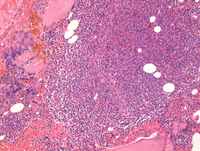

Biopsy in myeloma

The core biopsy shows hypercellular marrow replaced extensively by sheets of plasma cells which are easily identified at high power. Virtually no normal hematopoiesis is identified.